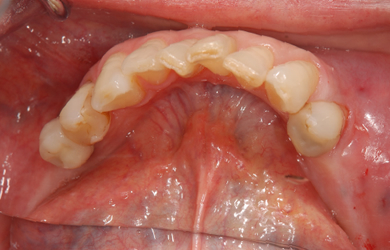

インプラントの症例写真 IMPLANT

スピードインプラント治療+セラミック治療

| 主訴 | 歯の無い部分にインプラント治療を受けたい。 | ||||||||||||||||||||||||||||||||

| 治療方針 | 抜歯と同時にインプラント治療を行うことにより、治療期間を短縮。 | ||||||||||||||||||||||||||||||||

| 治療内容 | インプラント4本(通常インプラント3本、抜歯即日スピードインプラント1本)、ハイブリッドセラミック5本 | ||||||||||||||||||||||||||||||||

| 総治療費 | 1,385,800円 | ||||||||||||||||||||||||||||||||

| 治療期間 | 4ヵ月+6ヶ月 |